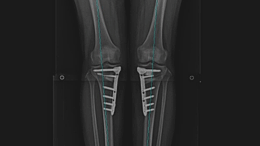

휜다리고정술